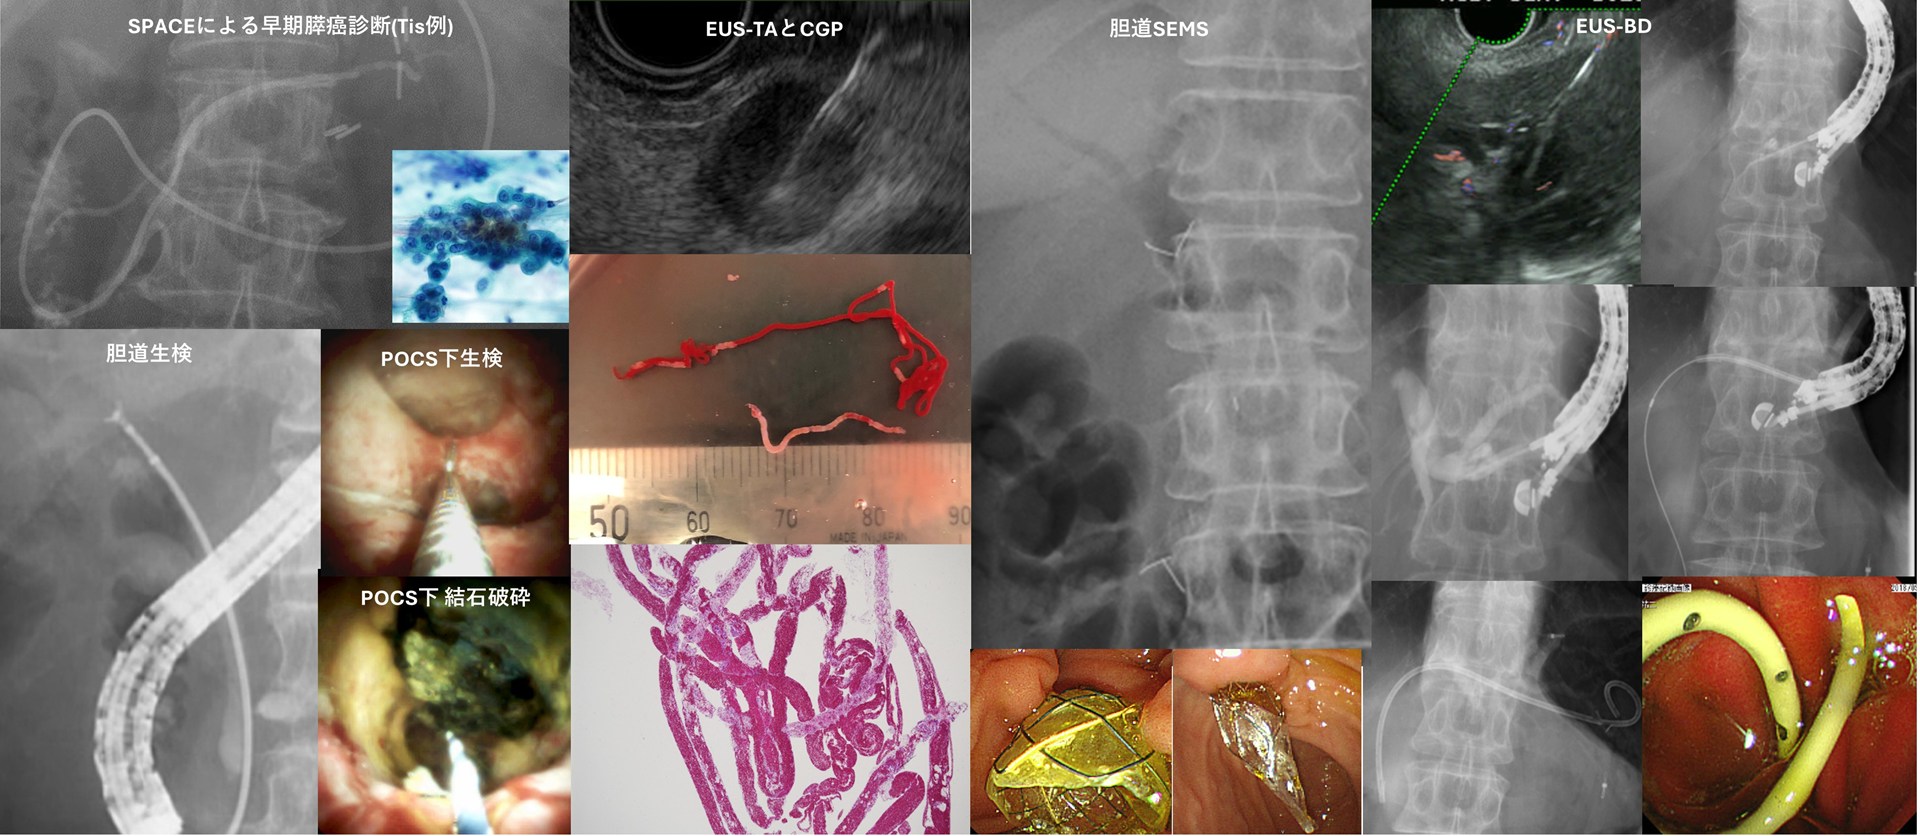

胆膵癌は消化器がんの中でも依然として予後不良であり、早期診断の困難さ、治療抵抗性、再発率の高さなど多くのunmet needsを抱えた領域です。一方で、診断技術、薬物療法、ゲノム医療の普及により、胆膵癌診療は今まさに変革期を迎えています。 私たち胆膵グループは、この変革を“現場発”で加速させることを目的に、Endoscopy-driven Pancreatobiliary Oncology(内視鏡が牽引する胆膵腫瘍診療)をコンセプトとして掲げています。 EUS/ERCPを核とした精密診断と内視鏡治療を出発点に、薬物療法・ゲノム医療・基礎研究を統合し、胆膵癌患者に還元される診療と研究を推進しています。

EUS/ERCPを基軸とした内視鏡診療と薬物療法との統合戦略

当グループの診療・研究の中核は、EUS/ERCPを基軸とした内視鏡診療と薬物療法の統合にあります。胆膵癌診療において、内視鏡診療は薬物療法の安全な導入と継続を支える不可欠な基盤であり、両者は相互に影響しながら治療成績を左右します。当グループでは、EUS/ERCPを用いた内視鏡診断や胆道ドレナージなどの治療を基盤に、術前治療や薬物療法を最適化する臨床研究を最重要テーマとして取り組んでいます。さらに、EUS-TAにより得られた検体の質向上にも取り組み、がん遺伝子パネル検査に耐えうる検体確保と提出体制を確立しています。 これまでに、胆道癌リンパ節転移に対するEUS-TAの有用性1)、肝門部胆管癌における初回ドレナージ戦略と予後の関連2)、EUS後胆管炎リスクの検討3)、膵嚢胞性病変に対する長期サーベイランスの重要性4)、ERCP下膵液細胞診の安全性と有用性5)など、内視鏡診療の質が胆膵癌治療全体のアウトカムに直結することを示す研究成果を報告しています。